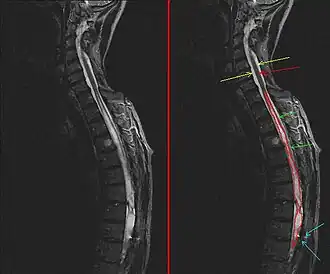

Syringomyelie is een zeldzame neurologische aandoening waarbij het ruggenmerg wordt aangetast, meestal vooral ter hoogte van de nekwervels, en het centrale kanaal in het ruggenmerg waardoor het wijder wordt.

De naam komt van het Grieks syrinx, een rieten buisje of fluitje en is gebaseerd op dit wijdere dan normaal kanaal dat bij pathologisch anatomisch onderzoek kan worden waargenomen. Tegenwoordig is de diagnose ook al bij levende patiënten te stellen door middel van MRI-onderzoek.